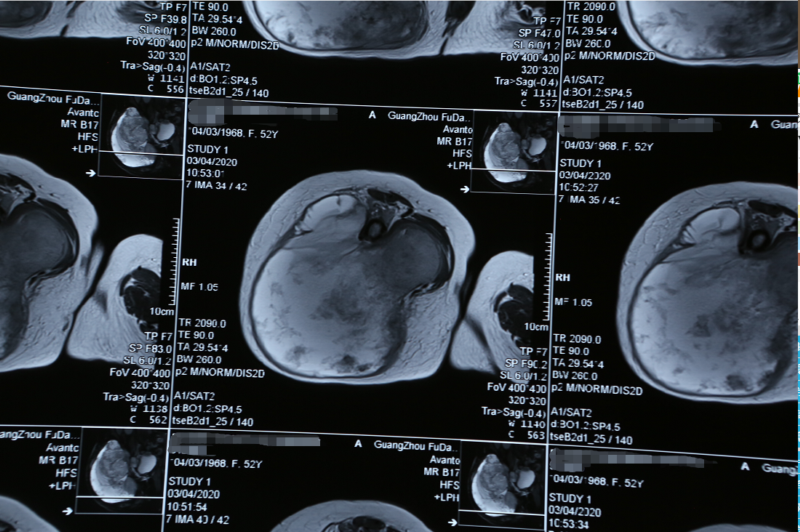

这是一位50多岁的菲律宾女性患者,15个月前发现患有右侧臀部软骨肉瘤,之后很快增大蔓延到整个右臀部和大腿后外侧导致大腿浮肿无法行走。曾经在马尼拉3家医院多次辗转求治,连菲律宾最好的外科医生们也都摇摇头表示无法治疗,最后患者在当地接受放化疗治疗效果甚微转至我院。由于肿瘤及淋巴互相融合包裹着血管干,手术难度非常大、风险极高,为尽可能保住患者的腿部,穆峰副院长联手南方医科大学的覃承和教授为患者制定合适的治疗方案。

10点50分,一道38厘米长的弧形切口纵跨了右侧骨盆区,达到大腿后外侧的上三分之一,手术组医生们开始向这个32.8*28.0*26.0cm的巨大广泛癌肿宣战。然后再一刀刀深入将皮肤脂肪和肌肉层层切开,切口约45公分创面约70公分。

此时已是下午13点25分,肿瘤被完整分离,保护皮瓣血管网,吸取部分的肿瘤坏死液化,止血,仔细探查分离已经被肿瘤侵犯的坐骨神经,整块切除肿瘤和被肿瘤侵犯的股骨大转子和部分骨盆壁。通过测量得知肿瘤大小为38*36*28cm,90%为实性,肿瘤重达约6Kg,其中抽取的囊液约2Kg。该患者原发于右臂骨盆,侵透骨盆进入盆腔6*7*8cm;右臂肌深面软骨肉瘤上延伸至髂嵴下至大腿后外侧上三分之一共38cm,前后宽度32cm,厚度28cm;侵犯股骨大转子和坐骨神经长约10cm。当穆副院长看到肿瘤已严重侵入盆骨后采用“刮骨疗伤”法,用手术刀轻轻刮去依附在骨头上及粘附在其他周围的肿瘤组织,切除进入盆腔8.0*6.5*5.8cm肿瘤达到了肉眼彻底整块切除肉瘤的效果。